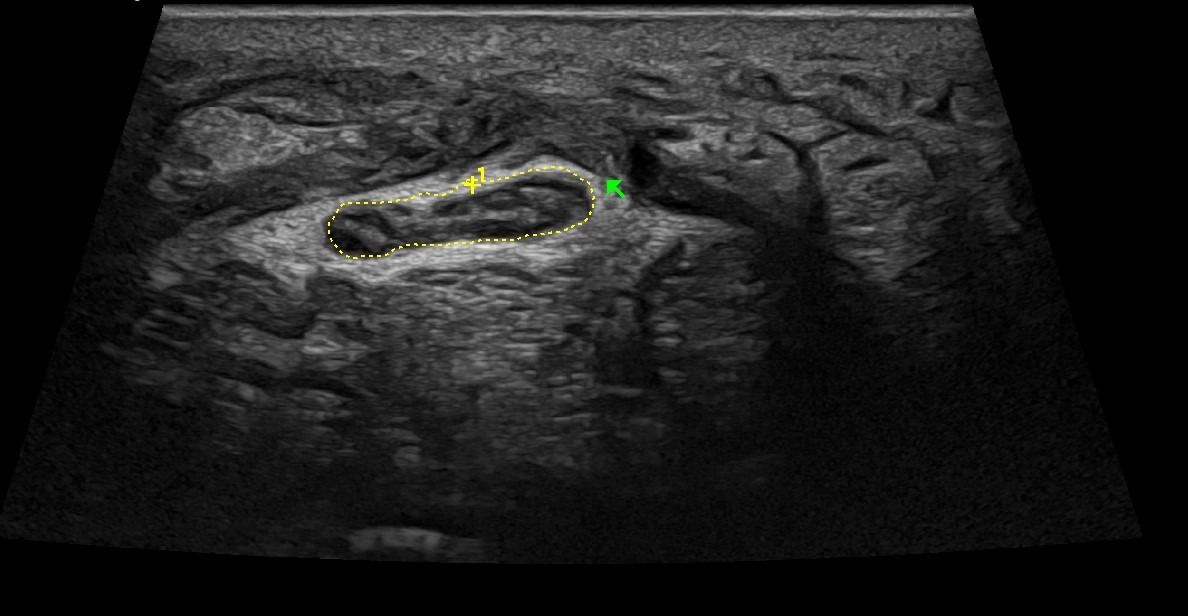

- Focal Lesions (tumors, neuromas)